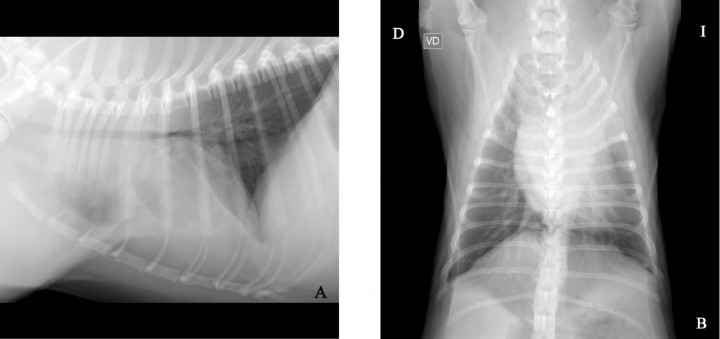

Se presenta en el Hospital Clínico Veterinario un perro de raza carlino, de 11 meses de edad, entero y 9,6 kg de peso, por un cuadro clínico desde hacía dos semanas con crisis de tos y disminución del apetito. El veterinario remitente le había pautado un tratamiento médico a base de codeína, doxiciclina y furosemida, respondiendo con una leve mejoría clínica. En el examen físico se evidenció, como único dato reseñable durante la auscultación torácica, un aumento de los sonidos traqueales y un sonido de roncus. El análisis sanguíneo reveló leucocitosis con desviación a la izquierda. Se realizaron radiografías de la cavidad torácica (Fig. 1).

<p>Tórax en un perro carlino de 11 meses e historia de tos y disminución del apetito. (<strong>A</strong>) Proyección lateral derecha. (<strong>B</strong>) Proyección ventrodorsal.</p>

Tórax en un perro carlino de 11 meses e historia de tos y disminución del apetito. (A) Proyección lateral derecha. (B) Proyección ventrodorsal.

Los hallazgos radiográficos que se han descrito en la torsión pulmonar incluyen derrame pleural, atelectasia lobar, consolidación lobar, desplazamiento mediastínico, pneumotórax y pneumomediastino. Estos signos se consideran inespecíficos, ya que también pueden observarse en diferentes procesos, como la neoplasia y la hernia diafragmática. En casos de efusión pleural, este líquido suele ser serosanguinolento o quiloso, con alto número de eritrocitos y leucocitos. Las anomalías radiográficas más características de esta patología son la presencia de un patrón de gas vesicular y un bronquio estrecho,[ Gicking JC, Aumann M. Lung lobe torsion. Compend Contin Educ Vet, 2011; 33: E1-E4. [PubMed] , Agut A, Carrillo JD, Seva J, Soler M, Laredo FG. What is your diagnosis? Lung lobe torsion. J Am Med Assoc 2013; 243: 333-335. [PubMed] ] aunque no se llegan a visualizar en todos los casos. En nuestro paciente únicamente se evidenciaba un aumento de la opacidad en la zona del lóbulo craneal izquierdo y leve efusión pleural, requiriéndose de pruebas de imagen más avanzadas como la tomografía computarizada (TC) para llegar al diagnóstico definitivo.